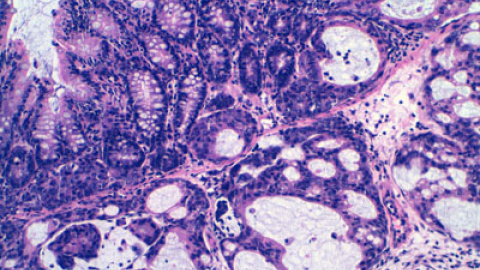

Un trabajo dirigido por el investigador del Instituto de Investigación Biomédica de Bellvitge (Idibell) Manel Esteller abre la puerta al tratamiento del cáncer a través de una novedosa vía: la estimulación, mediante la administración de un fármaco, de la producción de moléculas de microARN, una de las partes no codificantes del ADN. Estudios recientes han demostrado que cada vez está más claro que este tipo de ADN, antes conocido como ADN basura, juega un importante papel en el desarrollo de los tumores malignos.

Según explica Esteller, "en la mayoría de los tumores se puede ver un defecto en la producción de microARN". Por esta razón, el efecto observado con la enoxacina, el principio activo de un antibiótico muy utilizado en las infecciones de orina, es una buena noticia. El fármaco ha logrado producir más microARN tanto en células tumorales en el laboratorio (in vitro) como en tumores humanos insertados a ratones, según se recoge en el estudio publicado hoy en PNAS.